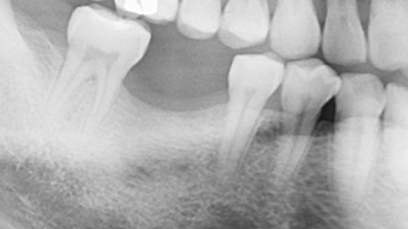

嚴重缺牙的後果? 不管是蛀牙導致的缺牙、退化所致的缺牙、意外造成的缺牙,嚴重缺牙最先會面臨到的問題是「營養流失」,長時間無法正常咀嚼、進食,吸收不佳的情況下,會導致營養不良。 此外,嚴重缺牙會讓口腔上下顎,無法對襯咬合,導致嘴巴無法正常閉合,除了影響美觀,長久下來,也會影響顳顎關節(temporomandibular joint)、咀嚼呼吸系統。 長時間缺後牙的後果? 「缺後牙沒有關係阿,反正看不到,用前面的牙齒咬就好」。這真的是大錯特錯的觀念,長時間缺後牙、錯失黃金治療期,後果,並非想像中的那麼簡單! 「上方後牙區缺牙」,會造成下顎後牙的牙齒往上移,導致錯位咬合,牙脊高度流失、上顎鼻竇腔膨大下墜。之後如果要植牙時,必須伴隨補骨、牙脊增高術或者上顎竇增高術。 「下方後牙區缺牙」,會造成上顎後牙的牙齒往下墜,導致錯位咬合,錯失黃金治療期,會讓牙脊高度、寬度流失,導致缺牙區沒有空間做假牙。 - 假牙的種類 2026.01.19